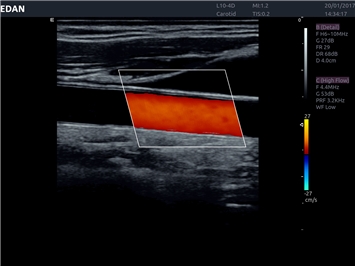

• Сосудистой диагностики

Цветовой допплер:

Да

Энергетический допплер: